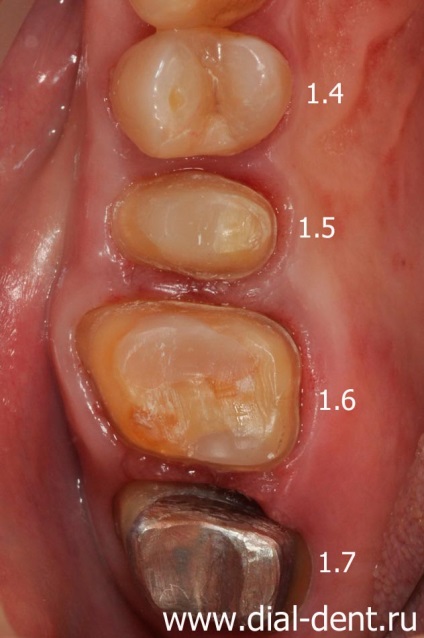

proteză

După un tratament de succes rădăcină canal dinților cu un microscop și înlocuirea umpluturile vechi, prosthodontist KV Verzilov a început de restaurare dentară.

Dinte 1.7 a fost grav avariată, astfel încât a fost restaurat cape, care va fi baza pentru coroana metalo-ceramic. În acest caz, coroana de metal opac ascunde complet urechea de metal din dinte.

Patru dinți (1.6, 1.5, 4.6, 4.7) vor fi acoperite cu coroane ceramice, care le va consolida și de a restabili funcția de mestecat și aspectul.

Dinți pregătite pentru coroane, eliminate din impresiile dintilor.